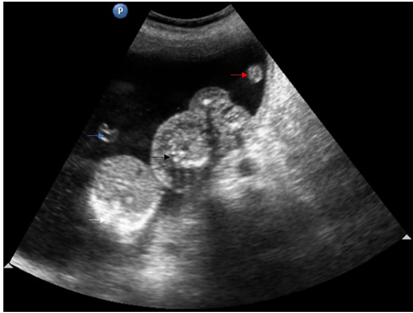

Figure 2,3 Trans-abdominal USG shows an abnormal fetus with grossly formed lower torso and lower limbs without any discernible visceral organs and an echogenic structure casting a distal acoustic shadow, probably representing the spine of the abnormal fetus (white arrow).

Figure 6 Trans-abdominal USG shows abnormal acardiac fetus with normal pumping twin and part of umbilical cords of both twins separately.

Video Trans-abdominal ultrasound showing intrauterine monochorionic diamniotic gestation with single anterior wall placenta. Normal pumping twin (white arrow) and abnormal a cardiac mass (black arrow) in the amniotic cavity on the right side and fetus with exencephaly in the amniotic cavity on the left with intervening amniotic membrane (red arrow).